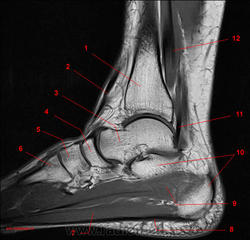

Рис. 13

1, Длинный разгибатель пальцев. 2, Б/берцовая кость. 3, Кубовидная кость. 4, Четвёртая плюсневая кость. 5, Мышца, отводящая мизинец стопы. 6, Пяточная кость. 7, Пяточное сухожилие. 8, Таранная кость.